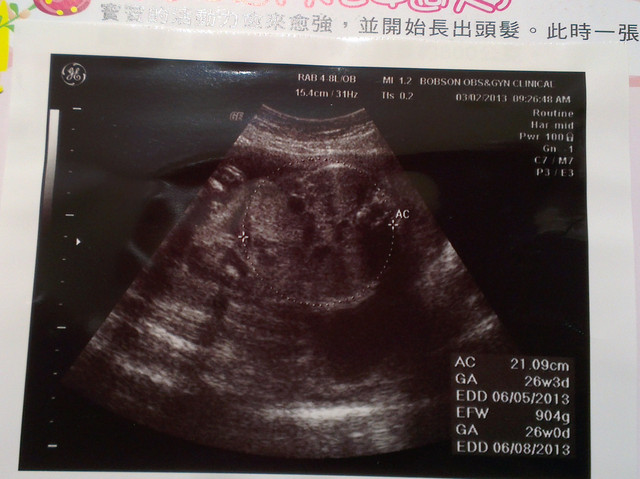

章魚寶滿5個月了

這時我們又滿心期待的想知道章魚寶是弟弟還是妹妹

不過這次產檢,醫生還是說照不出來

所以我五個月來產檢的時候,還不知道性別

這次產檢章魚寶的臉都往下看

沒有照到全部,因為他害羞啦

這時候章魚寶已經有重量囉

肚子重295g

這是五個多月時的照片,為23W左右

另外在附上章魚寶的產檢紀錄

分享給大家看喔